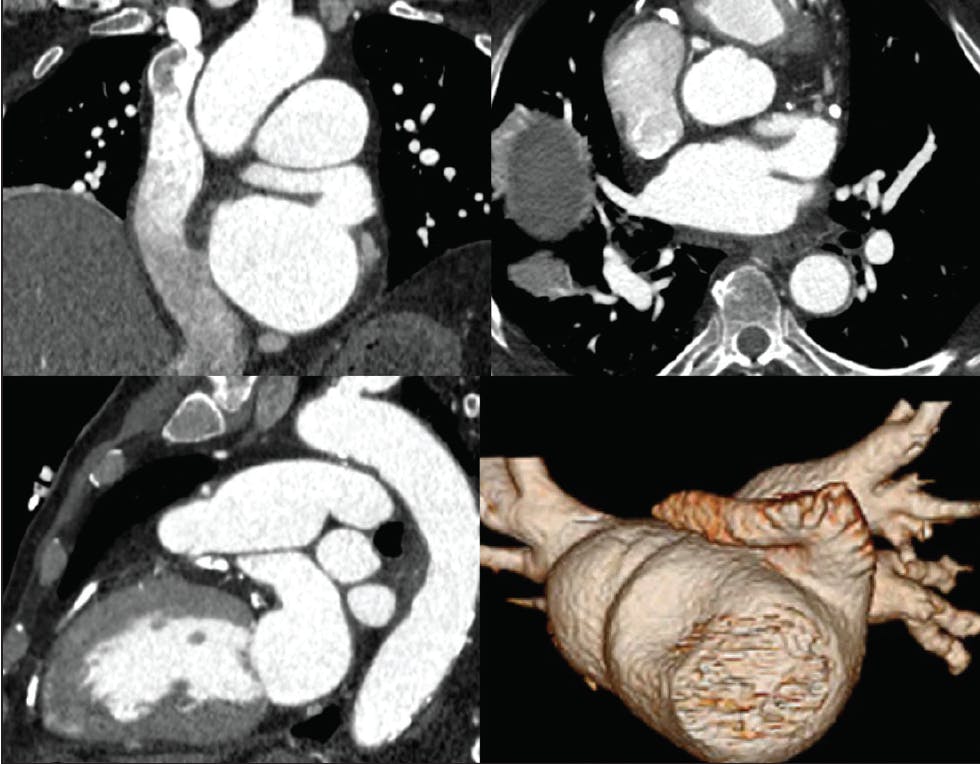

Figure 3. CCTA showing a challenging anterior chicken wing anatomy for LAAO.

LAA Topographic Orientation

The ability to close the LAA with endocardial devices is often hampered by its orientation. Anteriorly angulated LAAs are often more challenging to close due to the difficulties associated with gaining a coaxial alignment with the long axis of the appendage using fixed shape nonsteerable sheaths (Figure 3). Posteriorly oriented major lobes are more amenable to closure even when depth seems borderline. Hence, reporting the orientation of the major lobes of the LAA can aid in determining the feasibility of closure and selecting the appropriate device and/or sheath for the procedure.